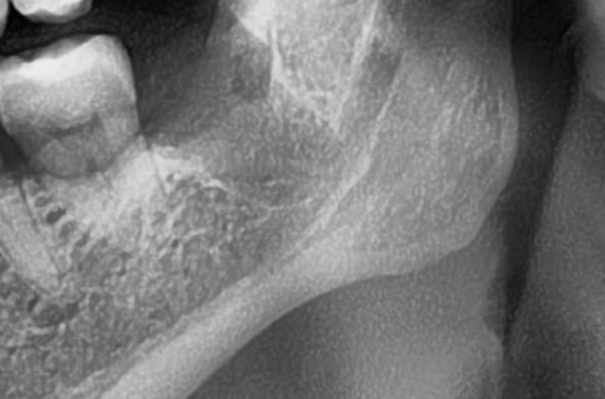

次にパノラマ写真を撮影してみると、左下の親知らずは歯ぐきの奥で生えているのが確認できました。